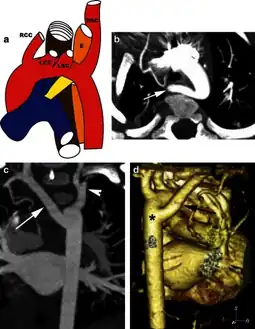

Aberrant subclavian artery on MR angiography.

Aberrant subclavian artery is a rare anatomical variant of the origin of the right or left subclavian artery. It is the most common congenital vascular anomaly of the aortic arch,[1] occurring in approximately 1% of individuals.[1][2][3]

This condition is usually asymptomatic.[1] The aberrant artery usually arises just distal to the left subclavian artery and crosses in the posterior part of the mediastinum on its way to the right upper extremity.[2] In 80% of individuals it crosses behind the esophagus.[2] Such course of this aberrant vessel may cause a vascular ring around the trachea and esophagus. Dysphagia due to an aberrant right subclavian artery is termed dysphagia lusoria, although this is a rare complication.[2][3] In addition to dysphagia, aberrant right subclavian artery may cause stridor, dyspnoea, chest pain, or fever.[1] An aberrant right subclavian artery may compress the recurrent laryngeal nerve causing a palsy of that nerve, which is termed Ortner's syndrome.[4]

The aberrant right subclavian artery frequently arises from a dilated segment of the proximal descending aorta, the so-called Diverticulum of Kommerell (which was named for the German radiologist Burkhard Friedrich Kommerell (1901–1990), who discovered it in 1936).[5][6] It is alternatively known as a lusorian artery.[1][3]

The evaluation of an aberrant subclavian artery can be done via CT angiography[7], which is a combo of CT scan with an injection of dye to produce images of blood vessels and/or tissues [8]